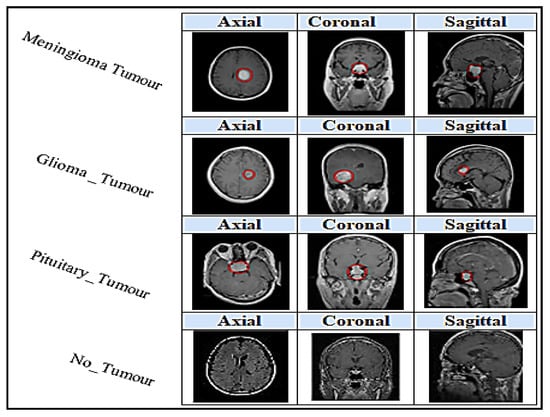

- The objective of the output layer:

- Not-Tumour;

- Meningioma Tumour;

- Glioma Tumour;

- Pituitary Tumour.